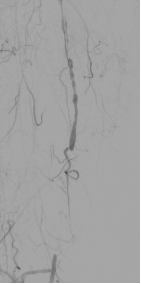

★ 病例 3

图:OA 基线造影

图:IVUS测量

图:Diamondback 360 减容

图:DCB扩张后 全程造影